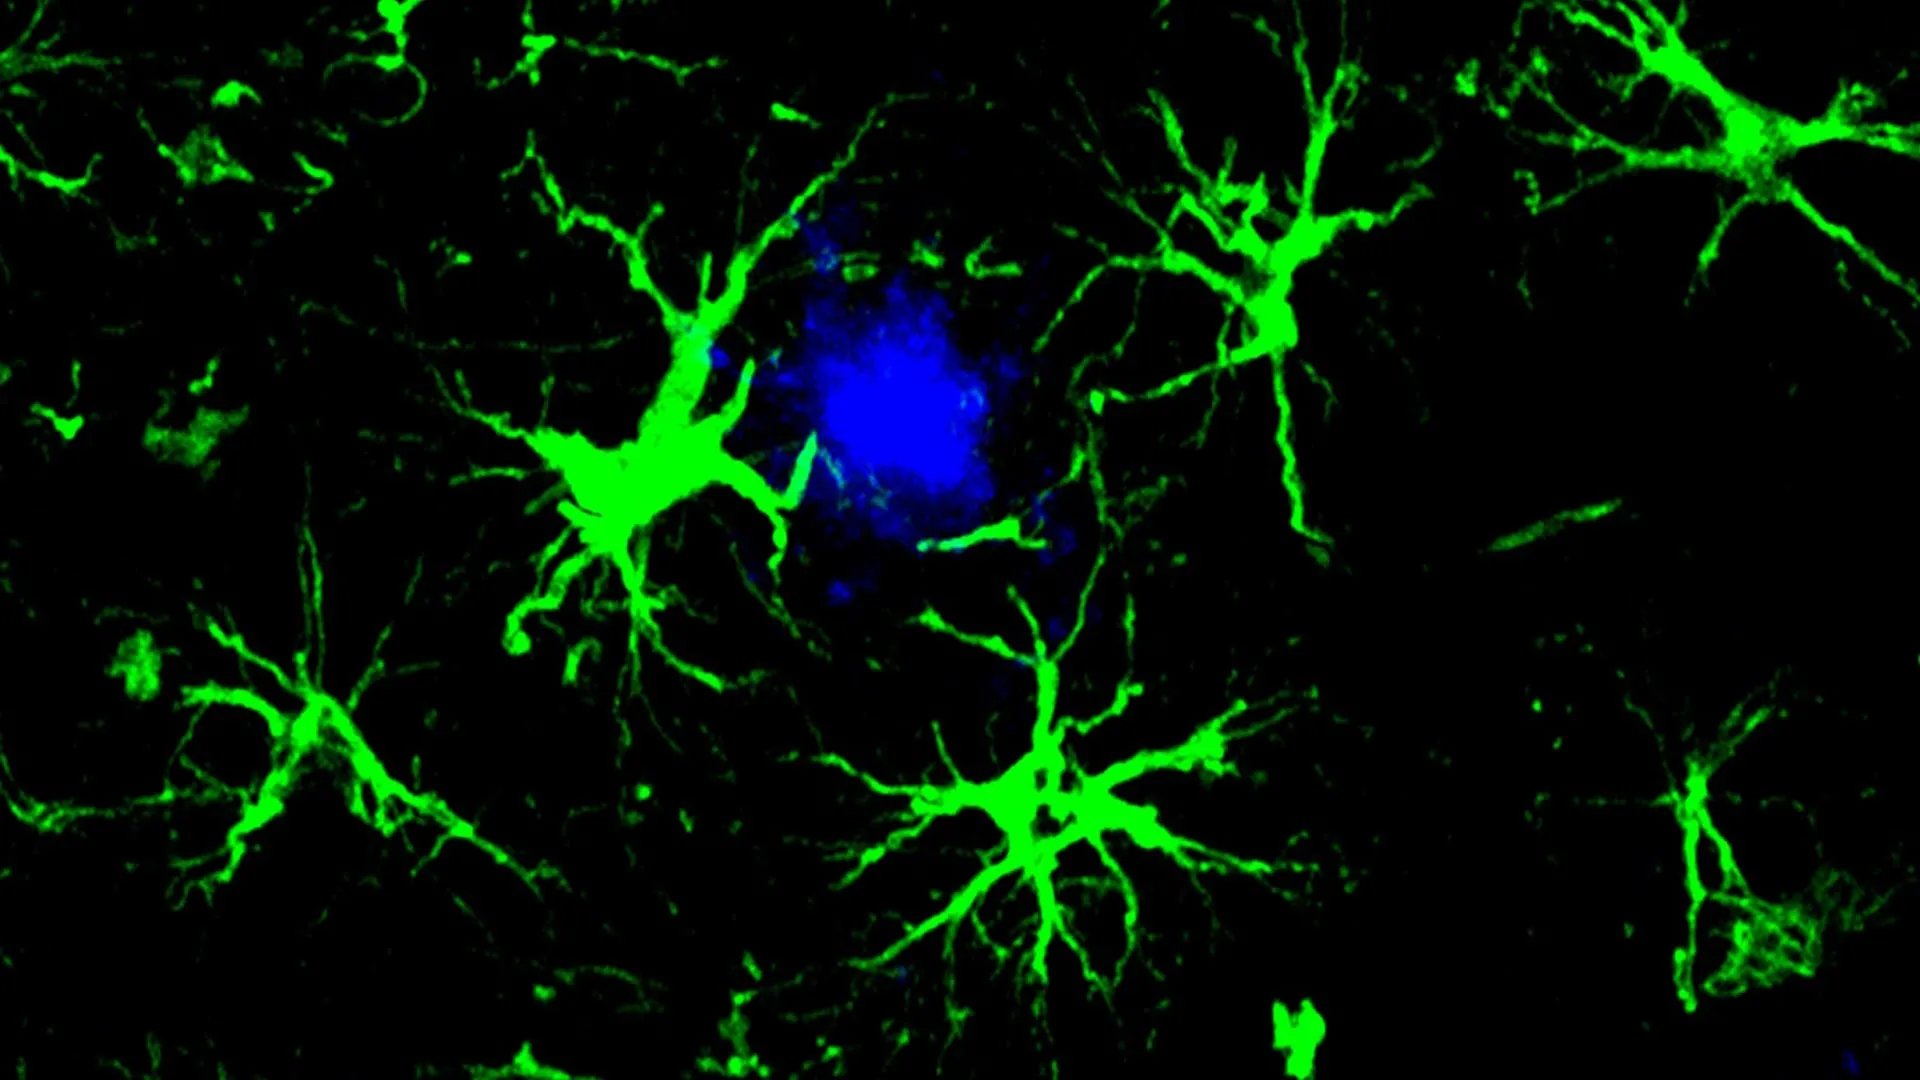

Astrocytes, the most abundant glial cells in the central nervous system, play vital roles in supporting neuronal health, regulating synaptic function, and maintaining the brain’s internal environment. In this novel strategy, researchers modified astrocytes by equipping them with a CAR "homing device." This engineered component allows the astrocytes to specifically identify and bind to amyloid-beta plaques. Once attached, these reprogrammed astrocytes act as highly effective cellular "clean-up crews," actively engulfing and degrading the harmful protein aggregates.

Under normal circumstances, the brain possesses its own sophisticated waste removal system, primarily managed by microglia, the resident immune cells of the central nervous system. Microglia are responsible for clearing cellular debris, misfolded proteins, and other harmful substances. However, in the context of neurodegenerative diseases like Alzheimer’s, these protective mechanisms can become overwhelmed. The chronic presence of amyloid plaques can lead to microglial dysfunction, rendering them less effective at clearing the accumulating pathology and potentially contributing to neuroinflammation, further exacerbating neuronal damage.

The team employed a harmless virus to introduce a gene encoding a CAR into astrocytes. This genetic modification effectively reprogrammed the astrocytes, imbuing them with the ability to recognize and bind to amyloid-beta proteins. Once the CAR receptor is expressed on the astrocyte’s surface, the cell gains the capacity to actively engulf and degrade the amyloid-beta.